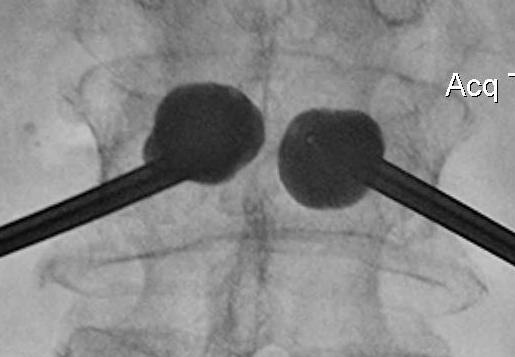

Technique

Insert a balloon first and inflate

- bilaterally into each pedicle

- will restore some anatomy

- then inject PMMA